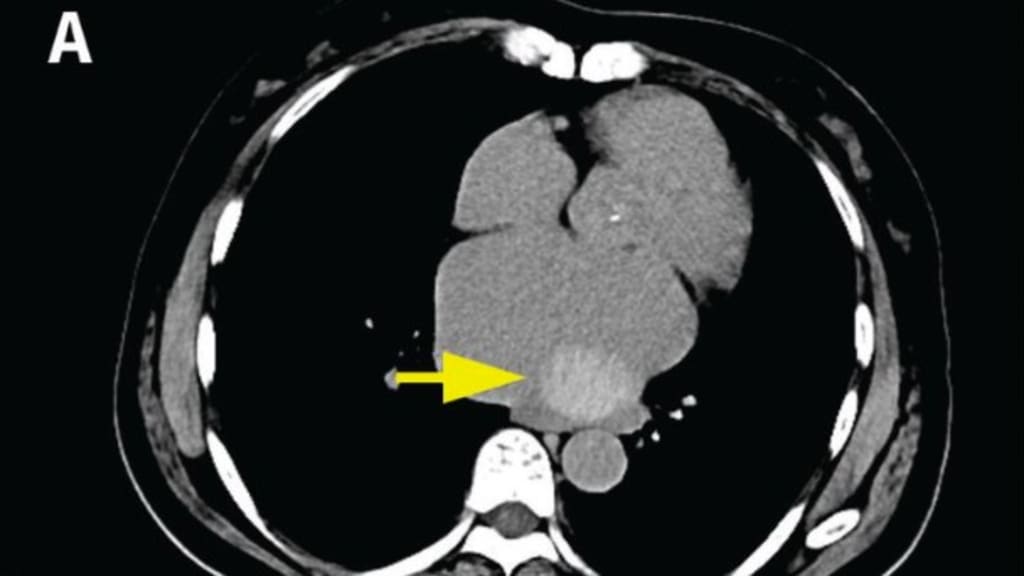

Eine axiale Computertomographie des Brustkorbs zeigt eine Masse im Herzen einer 60-jährigen Frau mit einem Durchmesser von 3,5 cm.

Eine 60-jährige Frau stellte sich zur präoperativen Untersuchung eines Knotens in der linken Lunge in der Thoraxchirurgie vor. Sie berichtete über ein leichtes Engegefühl in der Brust und Atemnot bei Anstrengung.1